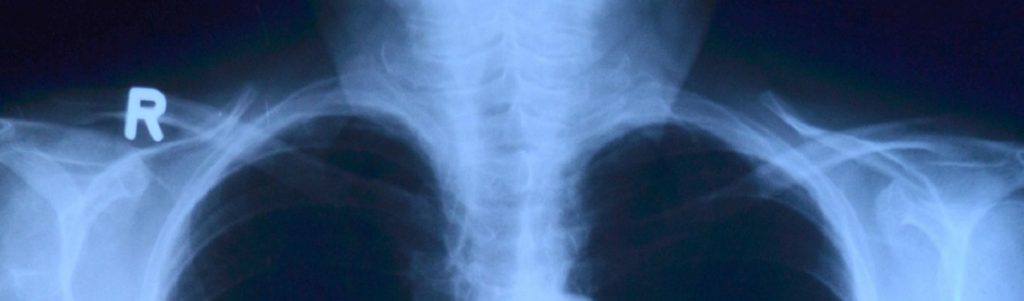

De nos jours, le travail des radiologues se densifie, malgré certains algorithmes de reconnaissance vocale qui allègent déjà un peu le travail. Mais avec l’augmentation de la rapidité de l’imagerie médicale, les médecins sont contraints d’étudier plus de dossiers par heure qu’auparavant. Les fondateurs de Raidium veulent résoudre ce problème en accélérant le temps d’analyse des radiologues grâce à des modèles d’IA. Il s’agirait ainsi de générer directement le bilan radiologique ou de détecter des anomalies sur les images, toujours sous le contrôle du médecin. De plus, avec cette compression du temps, les radiologues n’ont pas la possibilité d’étudier certains éléments comme la taille des organes et des tumeurs. La quantité de données à examiner est énorme, de même que la charge mentale des spécialistes.

Après avoir récolté des milliers de données auprès de différents hôpitaux, les cofondateurs vont maintenant proposer un modèle de leur produit, afin de montrer sa polyvalence. Raidium a déjà un partenariat avec les hôpitaux parisiens pour s’attaquer aux maladies du foie comme l’hypertension portale (complication majeure de la cirrhose) ou la Nash (stéatohépatite non alcoolique également nommée « maladie du foie gras »). Ces pathologies sont mal diagnostiquées et donc mal soignées. Le produit développé par la start-up pourrait aussi être utile dans le diagnostic de certains cancers. Quand la maladie se métastase, les analyses sont compliquées, car l’évolution des tumeurs dans les différents organes doit être étudiée, chose que les IA actuelles ne sont pas aujourd’hui capables de faire. L’IA proposée par Raidium pourra servir afin de réaliser des biopsies virtuelles pour la Nash, prédire de façon non invasive des marqueurs invasifs ou encore mieux évaluer le volume tumoral dans le cadre d’essais cliniques.